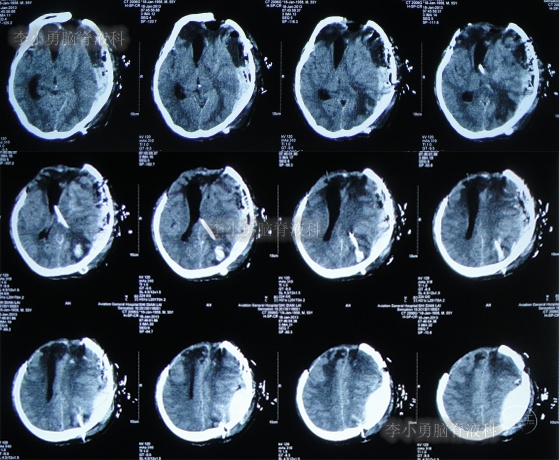

2012年11月1日(开颅术后126天即脑室腹腔分流术16天),转住入李小勇脑脊液科入院时:神志模糊,表情淡漠,肢体不能遵嘱活动,时常有癫痫发作;右额颞顶颅骨缺损,缺损相应区域局部凹陷,自右侧鼻唇沟至头顶有一疤痕,右侧额面部颅骨凹陷(图-6)。头颅CT:脑室腹腔分流术后改变,脑室扩张(图-7)。

图-7:入院时头颅CT

术后次日查头颅CT示脑室外引流术后(图-8);血培养(厌氧菌):溶血葡萄球菌感染。

图-8:2012年11月6日头颅CT

2012年11月23日(入院治疗23天),引流出血红色脑脊液(图-9);查头颅CT示脑室有缩小(图-10)。

图-10:2012年11月23日头颅CT

2013年1月14日(入院治疗75天),进行了左侧脑室腹腔分流术(图-11);

图-11:2013年1月14日术后头颅CT

2013年1月17日(入院治疗78天),晚上19点左右,患者突发意识障碍、右侧肢体偏瘫,头部外引流管流出粉红色液体,急查头颅CT示左额颞顶区硬膜下血肿,蛛网膜下腔出血(图-12)。于当晚急诊全麻下进行“左额颞顶硬膜下血肿清除术”。

图-12:2013年1月17日头颅CT

术后患者仍处于昏迷状态;次日2013年1月18日晨起,颅骨缺损处张力较高,复查头颅CT示术区无明显再出血,左顶叶硬膜外血肿,术区脑组织肿胀(图-13),当天进行了左额颞顶硬膜下血肿清除术后,左顶叶硬膜外血肿(图-14)。

图-13:2013年1月18日头颅CT

图-14:2013年1月18日术后头颅CT

2013年1月22日(入院治疗83天),患者术区引流管引流液极少,复查头颅CT脑室较前稍有扩张,右侧骨窗张力仍较高(图-15),进行了侧脑室外引流术(右)+左额颞顶硬膜下引流管去除术+左顶硬膜外引流管去除术。

图-15:2013年1月22日头颅CT

2013年1月25日(入院治疗86天),查头颅CT示脑室有缩小(图-16)。

图-16:2013年1月25日头颅CT